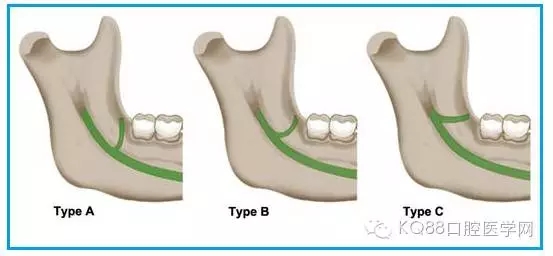

圖一 磨牙后區(qū)的形態(tài)學(xué)分類(綠色標(biāo)示):

A.水滴形;

B.細(xì)長型;

C.三角形。